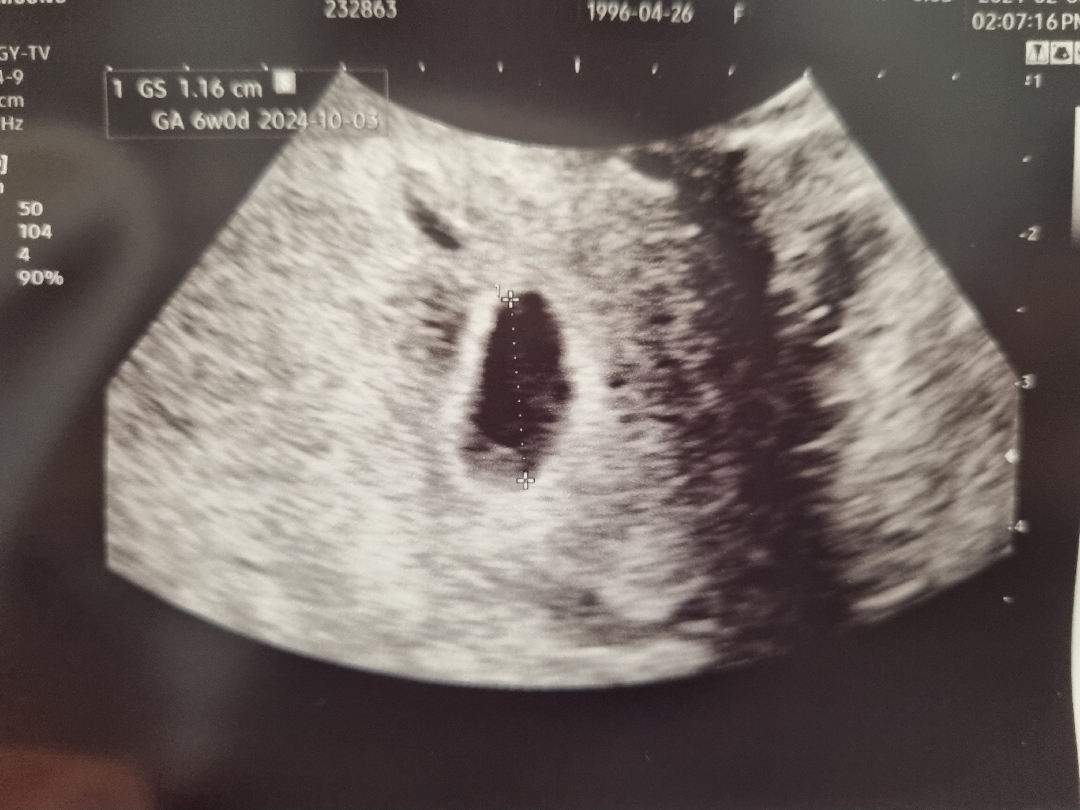

오늘 아기집 보고왔어요! 뭔가 모양이 생각한 동그란 모양은 아니었지만 그래도 잘 자리잡은 것 같아 다행이에요! 먹덧이 왔는지 뭘 안먹으면 속이 미식거리고 하필 그나마 땡기는 것도 면,빵 같은 밀가루 음식이다보니 급격하게 살이 2~3키로 쪘어요ㅜㅜ.. 아직 5주차밖에 안됬는데.. 안그래도 결혼 후에 7키로나 찐 상태인데 걱정이네요ㅠㅠ 저같은 경우 있으실까요??ㅠㅠ